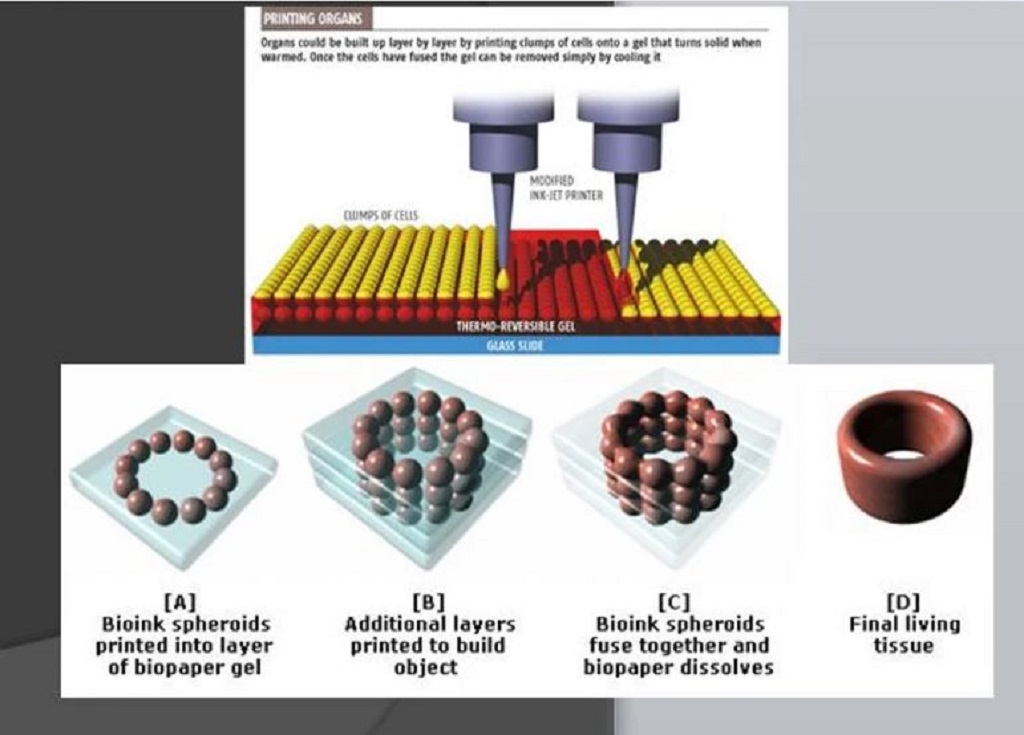

The Art Of Bioprinting

Bioprinting is a 3D printing technique that combines the technology of 3D printers with select biomaterials to imitate components of the body.